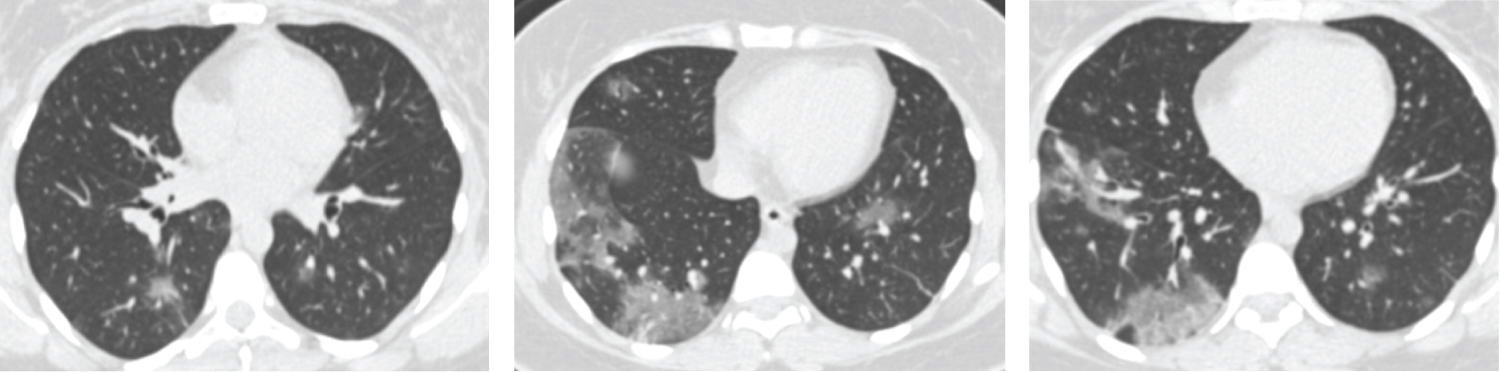

Figure 4: Female patient aged 37-years-old had negative initial reverse transcription-polymerase chain reaction results. Axial CT chest cuts shows bilateral ill-defined ground glass opacities with peripheral & sub-pleural in distribution seen at both upper and lower lung lobes these findings are highly suspected for COVID-19 (CORADS 4). View Figure 4

Figure 5: Male patient aged 60-years-old had positive initial reverse transcription-polymerase chain reaction results. Axial CT cuts show bilateral multi-focal ground glass opacities & smaller areas of consolidation are seen involving both lung fields with peripheral/subpleural predominance, this together with multiple subpleural lines this in keeping with viral pneumonia (COVID-19) (CORADS 5). View Figure 5